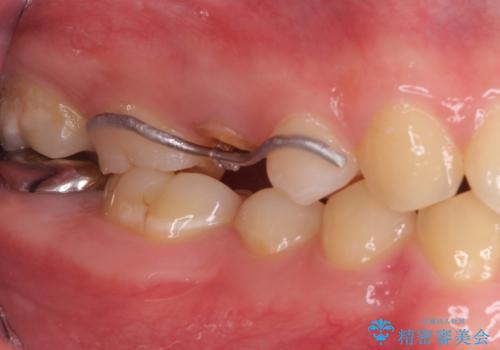

・約3か月ほど引っ張り出します。

・両どなりの歯に一時的にワイヤーを接着します。

・十分に引っ張り出した後、歯肉の手術が必要となります。